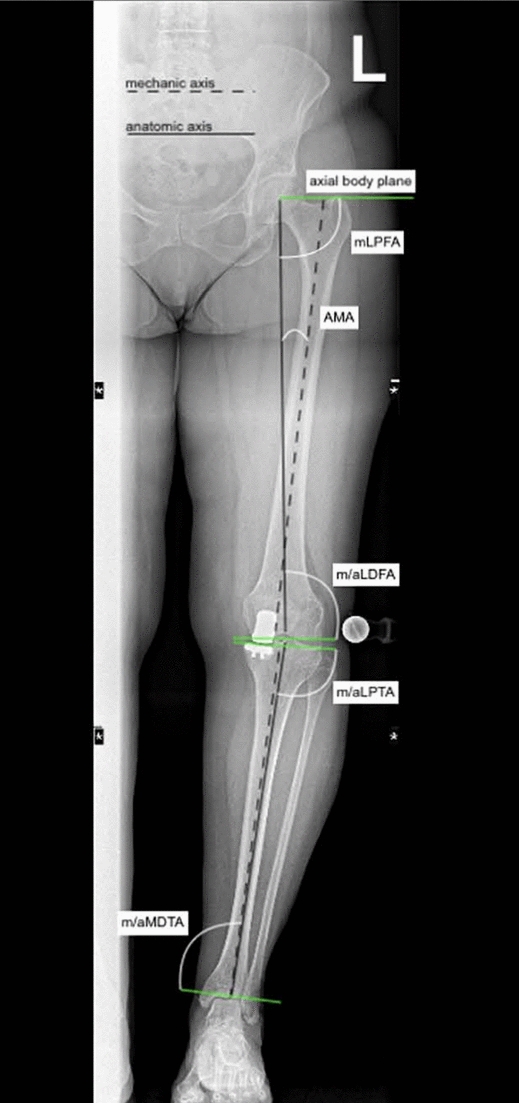

Methods: Imaging of patients who underwent revision surgery of a medial UKA to TKA for aseptic loosening of the tibial or femoral component was retrieved. Lower limb axes were evaluated using anteroposterior plain radiographs of the leg using the software MediCAD Knie 2D (mediCAD Hectec GmbH, Altdorf, Germany). The radiographic axes of revised patients were compared with established reference values, as defined by the MediCAD Knie 2D software and published literature, to identify common alignment patterns potentially associated with aseptic loosening.

Results: Data from 62 patients were analysed. Before the revision surgery, the joint line convergence angle (JLCA, P = 0.002) and the anatomical-mechanical angle (AMA, P < 0.0001) were statistically significantly greater than the corresponding reference values. In contrast, the mechanical lateral distal femoral angle (mLDFA, P < 0.0001), the mechanical and anatomical medial proximal tibial angle (mMPTA and aMPTA, P < 0.0001), and the mechanical and anatomical lateral distal tibial angle (mLDTA and aLDTA, P < 0.0001) were significantly lower than reference. No statistically significant difference was found in the mechanical lateral proximal femoral angle (mLPFA, P = 0.9) or in the mechanical axis deviation (MAD, P = 0.5) when compared to normative data.

Conclusion: Our cohort of patients revised from medial UKA to TKA for aseptic loosening frequently exhibited consistent deviations in lower limb alignment, particularly increased AMA and JLCA, and reduced mLDFA, mMPTA, and mLDTA. These subtle but recurrent patterns may alter load distribution across the medial compartment, contributing to implant micromotion and loosening. A detailed preoperative axis assessment may help identify patients at a higher biomechanical risk.